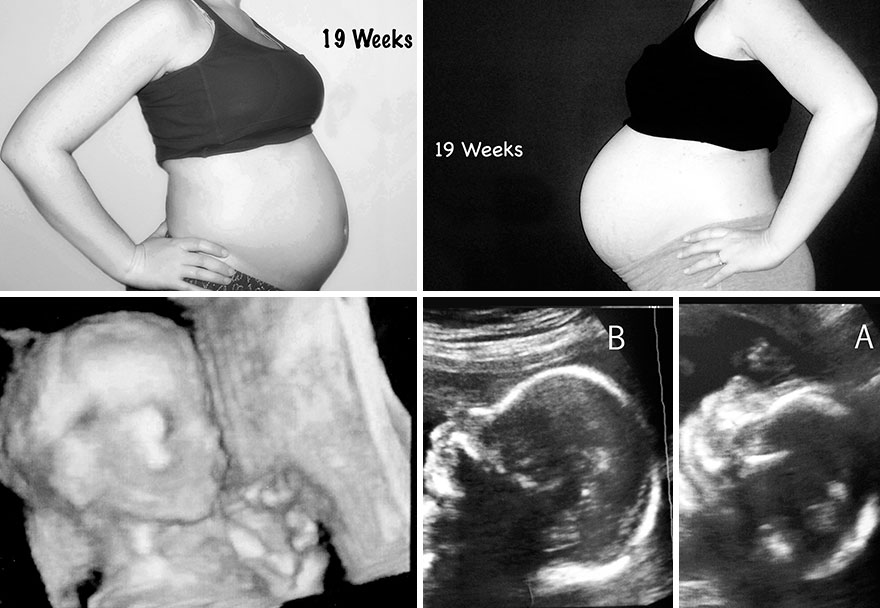

These pictures show the difference in my belly size with my singleton pregnancy and my twin pregnancy. It also shows the week’s corresponding ultrasound pictures. My husband and I continue to be amazed by all we’ve been through to get the amazing kids we have today. Even with the heartache and stress, I would not change a thing. Our three kids, now five years old (singleton) and two and a half (twins) are my world and are truly miracles that would never have been if not for the amazing advances of reproductive medicine. For that, we are truly thankful.

Nineteen weeks pregnant – Singleton (left) / Twins (right)